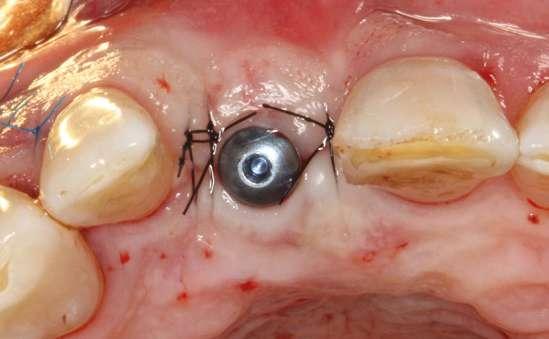

Figuras 1 y 2. Imágenes intraorales de la primera visita donde se hacen evidentes diferentes desgastes en los dientes anteriores y a mayor detalle crakcs en el esmalte, así como lesiones por abfracción en los cuellos de los dientes de los premolares y caninos superiores.

caso clínicoIMPLANTOLOGÍA

laterales se ponen de manifiesto aún más varias lesiones de esmalte que indican la parafunción en el paciente, unido a los desgastes excesivos en varias zonas (figuras 3 y 4). El paciente acude por dolor y movilidad en la pieza 11, que se ha incrementado en los últimos días, además de sensación de “diente crecido” que como podemos ver en las fotografías iniciales es real, ya que el diente se encuentra ligeramente extruido en relación con el contralateral. Estos signos parecen indicarnos una fractura o fisura. En la fotografía oclusal, podemos observar el desplazamiento del diente debido a la movilidad (figura 5). Posteriormente se realiza un sondaje positivo de la pieza, que lleva a 11 mm por lo que se confirma la sospecha de fractura y se procede a la exodoncia del diente, realizándose una regeneración posterior del alveolo con PRGF-Endoret y

esperándose 4 semanas hasta el cierre de los tejidos blandos y la neoformación ósea inicial para la colocación de un implante temprano. Cuatro semanas después, realizamos un cone-beam de control para conocer el estado del tejido óseo y poder planificar el implante. En el corte seccional observamos que se ha regenerado por completo el lecho receptor y tenemos un hueso óptimo para la inserción del implante, que por el tiempo transcurrido además es muy sencillo de expandir, con el propio implante generándose una expansión atraumática que nos permitirá ganar anchura ósea y con un implante estrecho de 3,5 mm de diámetro logramos posicionarlo sin dañar la desembocadura del nervio incisivo (figura 6). En cuanto a la longitud, con 7,5 es suficiente, no necesitándose un tamaño mayor para un correcto rendimiento biomecánico posterior.

Colocamos el implante generándose una ligera expansión vestibular, como mostramos en las imágenes intraoperatorias, para posteriormente ser sobrecorregido con hueso autólogo obtenido del fresado, embebido en PRGF-endoret y lograr una mayor anchura vestíbulo-lingual en la zona de colocación del im-

plante, clave para lograr una mejor estética y además un mantenimiento de los tejidos periimplantarios a largo plazo. En la fase quirúrgica colocamos además el transepitelial unitario para la realización de la carga inmediata y la colcación de un provisional atornillado horas después de la cirugía (figuras 7-14).

Figuras 7 y 8. Perforación inicial y colocación del implante expandiendo la zona vestibular.

Figuras 9 y 10. Visión vestibular tras la inserción del implante y colocación del transepitelial unitario para comenzar la carga inmediata.

Figuras 11 y 12. Sobre-corrección vestibular y cierre primario de los tejidos con un monofilamento no reabsorbible alrededor de la tapa de protección del transepitelial.